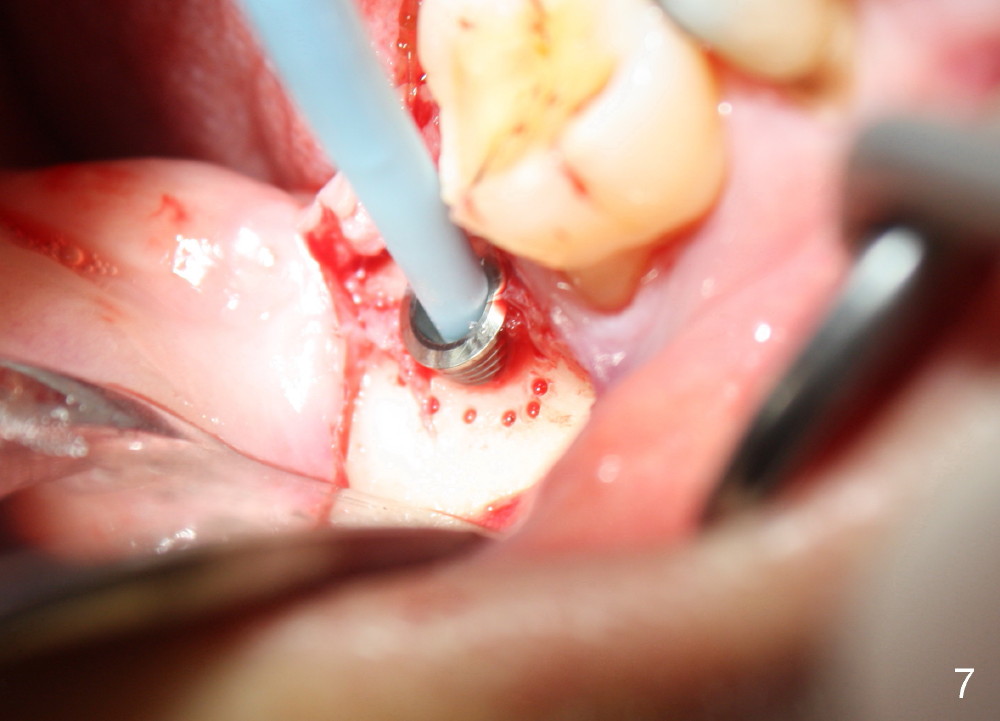

A 57-year-old lady returns for #31 implantation. The vertical edentulous space is limited, as the opposing tooth is supraerupted (Fig.1 arrow). Preop PA is critical (Fig.2), since it is used to measure the bone height (Fig.3: 12 mm). The length of the implant is expected to be 10 mm. The initial osteotomy depth is 8 mm (Fig.4); it appears that the trajectory should be adjusted. Osteotomy increases following depth and angulation adjustment (Fig.5: 4.5x10 mm drill). The submerged implant (5.3x10 mm) is placed with insertion torque approximately 35 Ncm (Fig.6). The buccal microthreads are exposed (Fig.7); to prepare for bone graft, the buccal plate is decorticated. Following placement of freeze dry mineralized allograft, collagen membrane is fixated by a healing screw (Fig.8). The incision is closed by 4-0 Chromic gut sutures and perio glue (Fig.9).

Bone-level implants offer two options after placement (stages 1 and 2). If the insertion torque is high and there is sufficient vertical edentulous space, a healing abutment is placed (stage 1). No surgery is required for restoration. Otherwise, the implant should be buried, as shown in this case. Two mini-implants are going to be placed to intrude the opposing supraerupted tooth. In fact, the orthodontic intrusion is quite difficult. Finally the intrusion apparatus has to be removed prior to chemotherapy for breast cancer. PAs taken 1 year 3 months (Fig.10) and 1 year 9 months (Fig.11, 6 months post cementation) postop appear to show that there is coronal bone loss. An abutment with short cuff (Fig.11 *) is chosen for final crown (C). Ideally the implant should have been placed deeper (Fig.7) for easy restoration. Pre-op examination and diagnosis are critical.